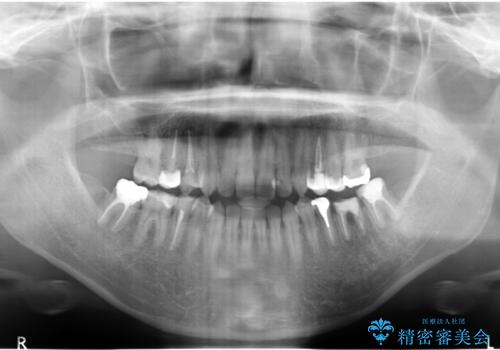

上顎の左右の奥歯が欠損(虫歯で失ったとのこと)していた部位はインプラント治療をお勧めしましたが、選択されませんでした。

その代わり、放置すると悪くなる部分は積極的に直し、高さがない部分はしっかり手術を行いかぶせました。

支える歯の本数が少ないうえに歯ぎしりもあるため、虫歯を治したとしても歯が割れるリスクがあります。

虫歯治療後にナイトガードを作成いただき、就寝時使用もらい予防を図っています。